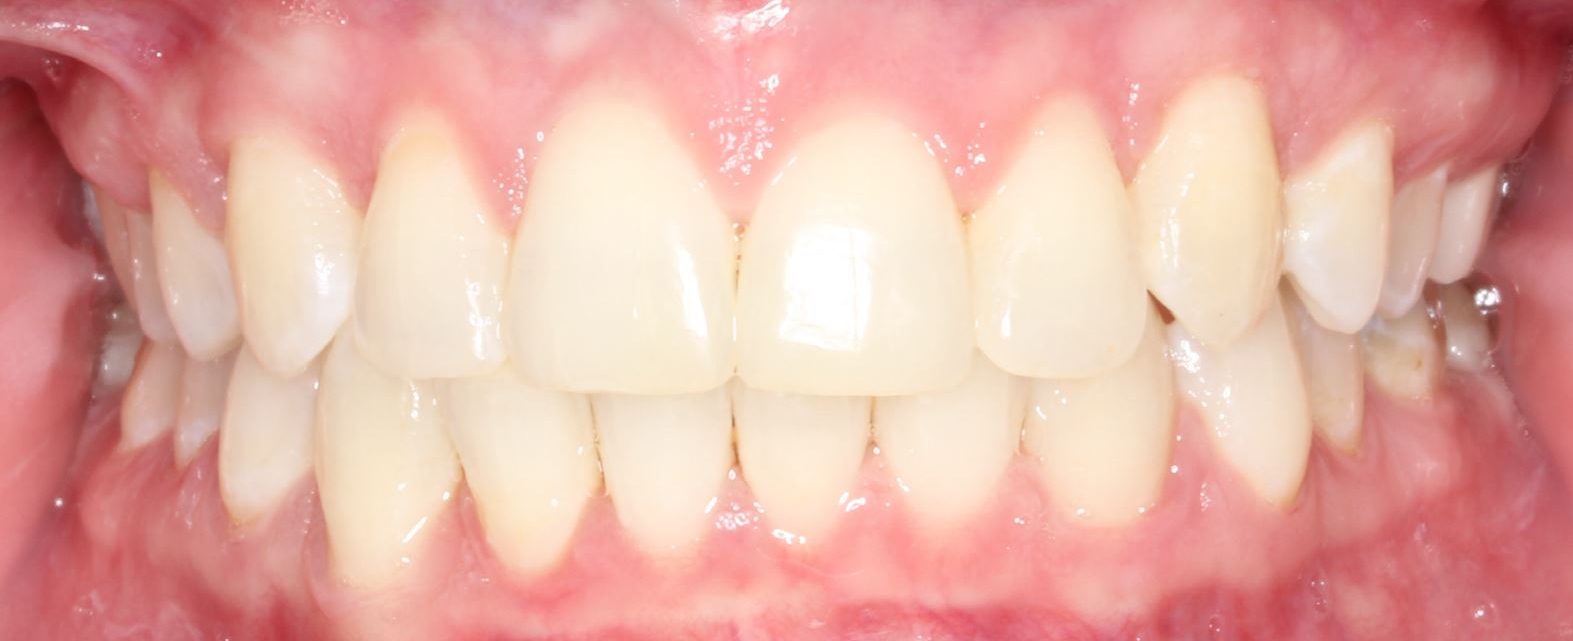

Conventional Braces